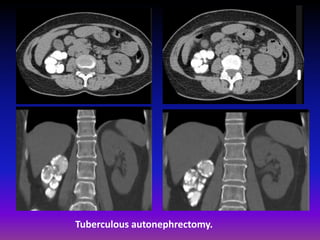

CT is the most sensitive modality for visualizing renal

calcifications and CT IVP is more sensitive at

identifying all manifestations of renal tuberculosis .

Early papillary necrosis (single or multiple) resulting

in uneven caliectasis progressive multifocal strictures

can affect any part of the collecting system

generalized or focal hydronephrosis mural thickening

and enhancement poorly enhancing renal

parenchyma, either due to direct involvement or due

to hydronephrosis

end stage progressive hydronephrosis results in very

thin parenchyma, mimicking multiple thin walled

cysts amorphous dystrophic calcification eventually

involves the entire kidney (known as putty kidney).

Tuberculous autonephrectomy.